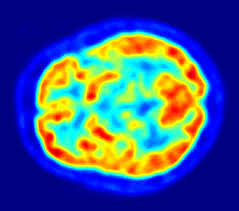

• Tomografía por emisión de positrones TEP

Tomografía por emisión de positrones TEP

Técnica de neuroimagen no invasiva que brinda imágenes de la actividad cerebral